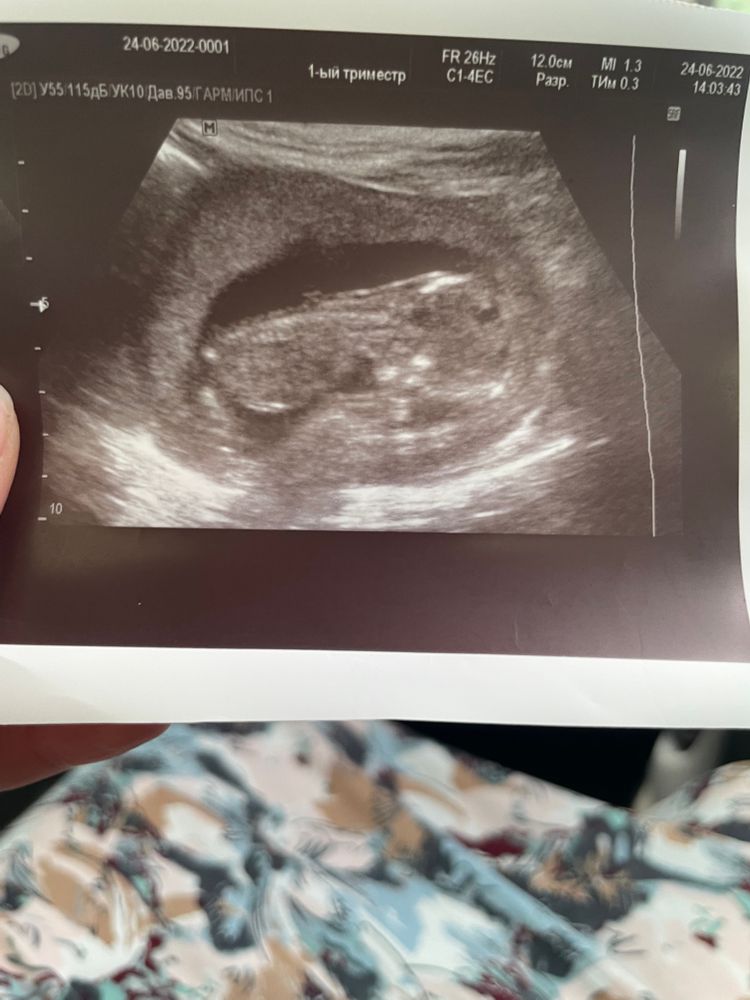

Девочки это мое 3 узи за все 13 нед…. Так как была необходимость и все три раз в разный период моя бусинка лежит в таком положении скажите пожалуйста почему так???по первому узи в меня 13 нед 3 дня по второму 13 нед 1 день а делала сегодня то показывает 13 нед 6 дней

Муся, я имею ввиду что он лежит так что спинка верх а ручки ножки вниз (будто как на животике) а у других вижу наоборот лежат на спинке